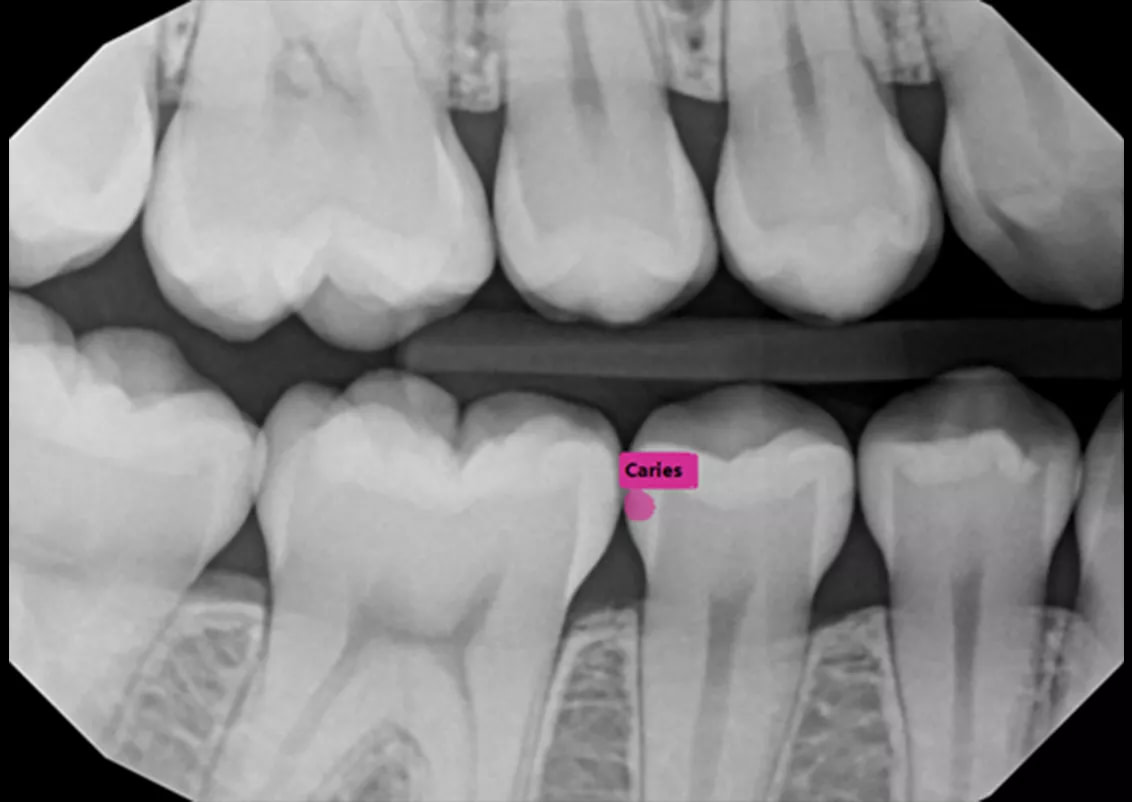

- Automatically file and organize radiographs

- Detect caries, calculus, bone loss, and other pathologies